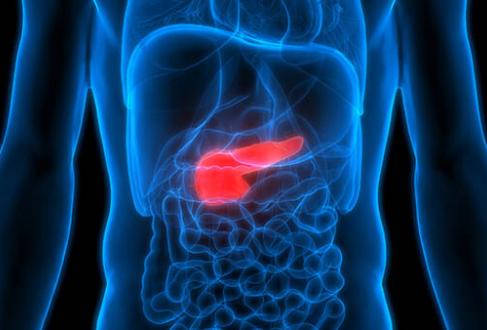

UT Health San Antonio doctors provide new hope for pancreatic cancer patients

UT Health San Antonio Multispecialty and Research Hospital became the first in South Texas to use an emerging and less-invasive treatment called radiofrequency ablation on a comorbid patient with a pancreatic cancer tumor that couldn’t be removed by surgery.

UT Health San Antonio creates innovative organoid for advancing understanding of pancreatic cancer

Pancreatic ductal adenocarcinoma (PDAC), a certain type of pancreatic cancer, is a ruthless killer with an average five-year survival rate of less than 10%. Most patients are diagnosed at a late stage when the cancer has already spread throughout their bodies. And the problem is only growing worse. By 2030, pancreatic cancer is expected […]